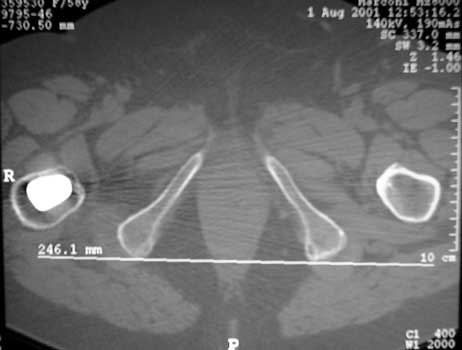

Femoral version measure by CT. Axial images are obtained through the hips and femoral condyles. A reference line is drawn through the posterior aspect of the medial and femoral condyles (Fig A). A second line in drawn through the axis of the neck of the femoral prosthesis. These lines are superimposed, and the femoral version angle is measured. (Fig B)